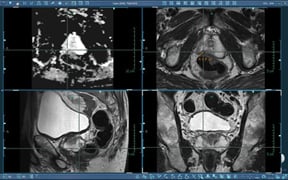

Multiplanar T2-weighted images and ADC map.

Six months later, the second TRUS biopsy was performed with 12 core samples. Again, no malignancy was found and follow up was once again recommended. DRE was also performed with no palpable abnormalities. Since his PSA levels remained elevated, the patient was referred for a diagnostic MRI study. The examination was performed on a 3.0T MRI scanner with the body array coil in a dual-coil setup. Multiparametric imaging sequences were acquired including high-resolution, multiplanar T2-weighted anatomical images.

Diffusion-weighted images with b-values of 50, 500 and 800 were acquired and an ADC map was generated. The study was then imported to DynaCAD for Prostate for analysis and interpretation.

Image Results: A suspicious area was identified on axial T2. Based on these findings, MR-guided biopsy was recommended. MR-guided prostate biopsy was performed with DynaCAD for Prostate and DynaTRIM.